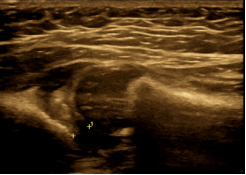

1、超声在肌肉、肌腱损伤中的应用:肌骨超声能够清晰显示肌间隔及细小的肌纤维束,用于判断肌肉及肌腱病变。肌骨超声在评估软组织损伤、肌肉微小撕裂、肌腱断裂、韧带损伤及神经的损伤方面具有独特优势。对于隐形骨折、撕脱的微小骨折、软骨骨折、骨骺坏死等也是具有优势,诊断并量化软组织、肌肉、肌腱、韧带损伤的严重性和损伤范围,并清晰显示肌肉、肌腱断裂的断端及回缩断端的部位。对于软组织、肌肉、肌腱的劳损、慢性退行性病变肌骨超声可显示其细微结构变化。

图1 微骨折